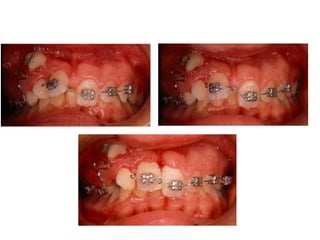

TRANSPOSIÇÃO TOTAL - CANINO COM INCISIVO LATERAL MANOBRAS PARA CORREÇÃO DA ROTA DE ERUPÇÃO